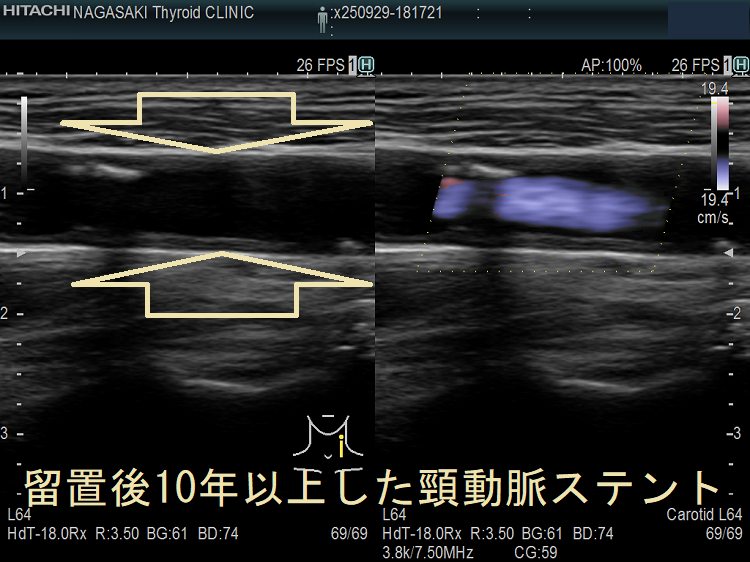

甲状腺機能低下症/潜在性甲状腺機能低下症/橋本病、糖尿病などでは動脈硬化が進み、頚動脈プラークにできた血栓が脳へ流れて脳梗塞。最悪、頚動脈自体の閉塞も。血管エコーでプラークを探す。動脈硬化血管は硬くもろく、大動脈では血圧に負けて大動脈瘤に。頸動脈閉塞度70%以上でカテーテル手術、ステント留置。時間が経つとステント上に新たなプラーク形成。内頸動脈ステント留置時、ガイドワイヤーで外頸動脈枝の上甲状腺動脈穿孔おこした報告あり。コレステロール/脂質塞栓が、網膜動脈を完全/不完全閉塞すると黄色斑(ホレンホースト斑)が生じる。

脳卒中治療ガイドライン 2021〔改訂2025〕では、軽度~中等度の頸動脈狭窄に頸動脈ステント留置や手術によるプラーク除去(頸動脈内膜剥離術)を行わないよう勧めています。

高度狭窄か脳梗塞を伴う中等度以上狭窄に対し、頸動脈ステント留置よりも手術によるプラーク除去(頸動脈内膜剥離術:CEA)を推奨しています。手術不能例には頸動脈ステント留置(CAS)。